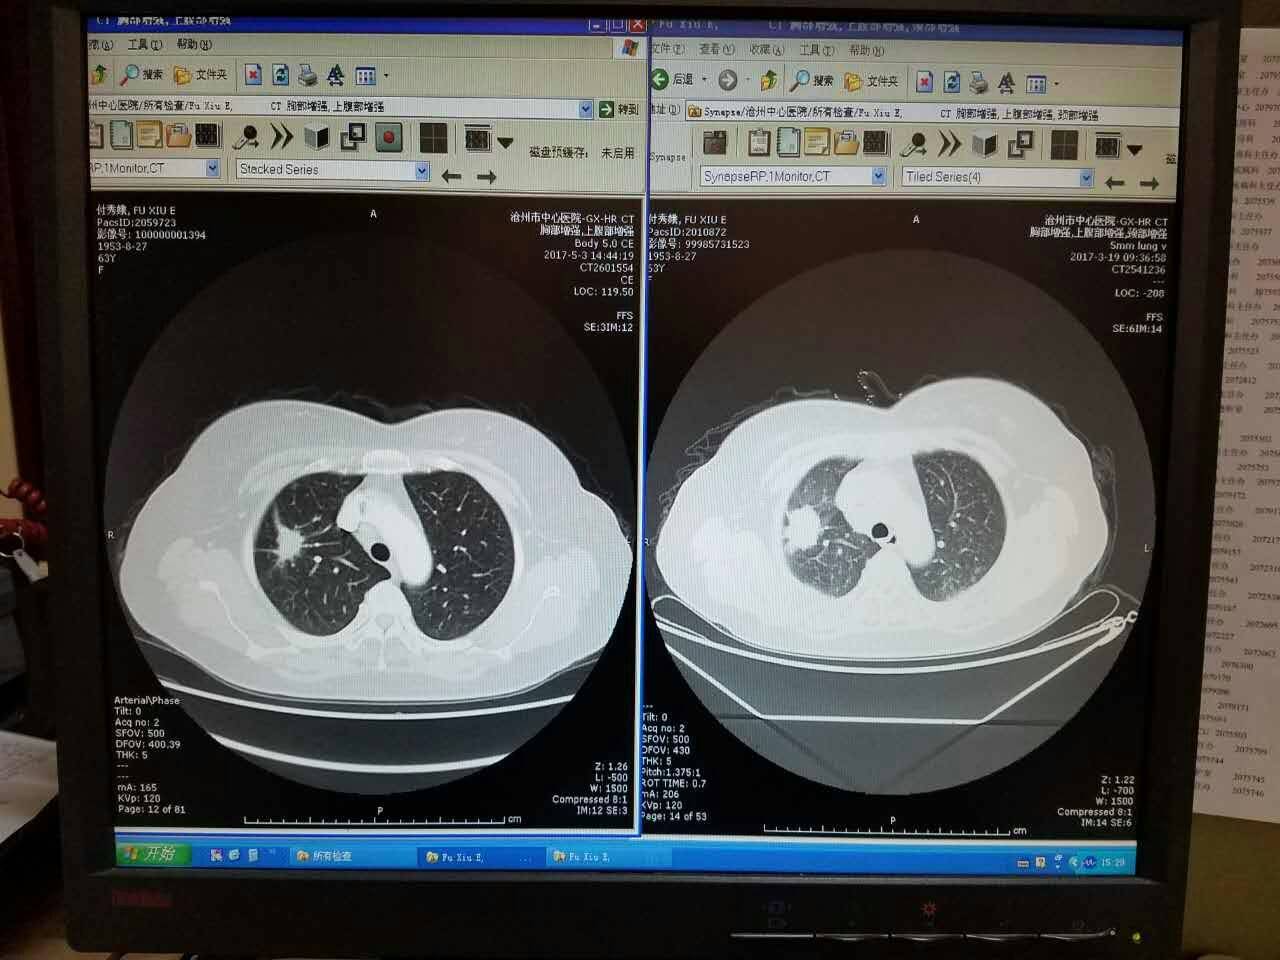

母亲服药35天后,第一次复查结果出来了,看到肿瘤明显缩小,血液检测ca数值明显下降!让我们对妈妈的康复越来越有信心了,希望特罗凯能给我们奇迹!

每张影像是3月19和5月3日的对比图,很高兴数值都有所下降